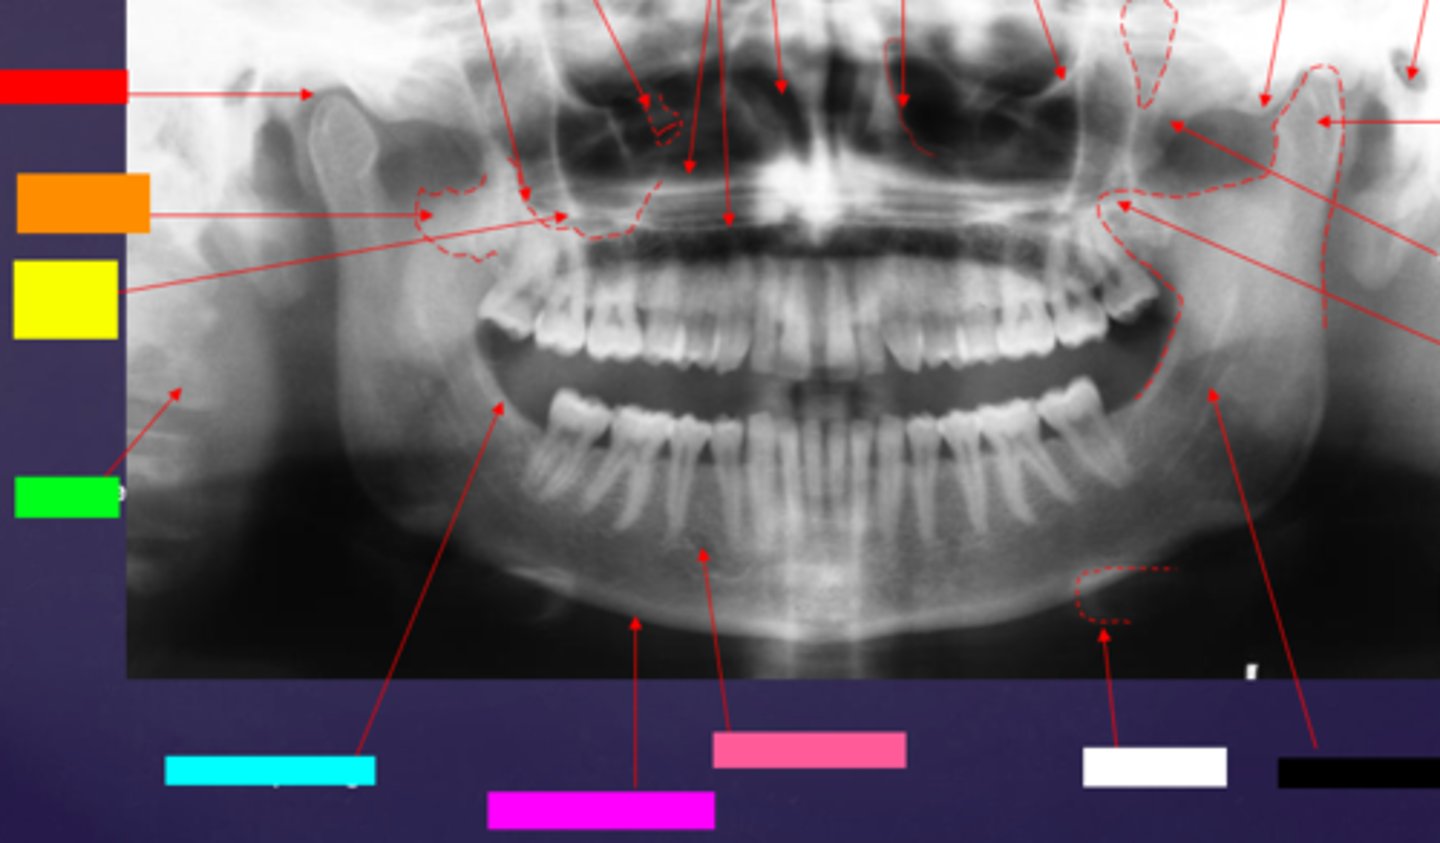

ID the hard tissue anatomy indicated by the arrow pointing from the red box:

floor of max. sinus

ID the hard tissue anatomy indicated by the arrow pointing from the orange box:

infra orbital canal and foramen

ID the hard tissue anatomy indicated by the arrow pointing from the yellow box:

hard palate/floor of nasal fossa

ID the hard tissue anatomy indicated by the arrow pointing from the green box:

nasal fossa

ID the hard tissue anatomy indicated by the arrow pointing from the light blue box:

ant. wall of max. sinus

ID the hard tissue anatomy indicated by the arrow pointing from the dark blue box:

coronoid process

ID the hard tissue anatomy indicated by the arrow pointing from the hot pink box:

infra orbital rim

ID the hard tissue anatomy indicated by the arrow pointing from the pink/salmon box:

pterygomaxillary fissure

ID the hard tissue anatomy indicated by the arrow pointing from the brown box:

external auditory meatus/ear canal

ID the hard tissue anatomy indicated by the arrow pointing from the white box:

articular eminence

ID the hard tissue anatomy indicated by the arrow pointing from the black box:

mandibular condyle

ID the hard tissue anatomy indicated by the arrow pointing from the gray box:

zygomatic bone